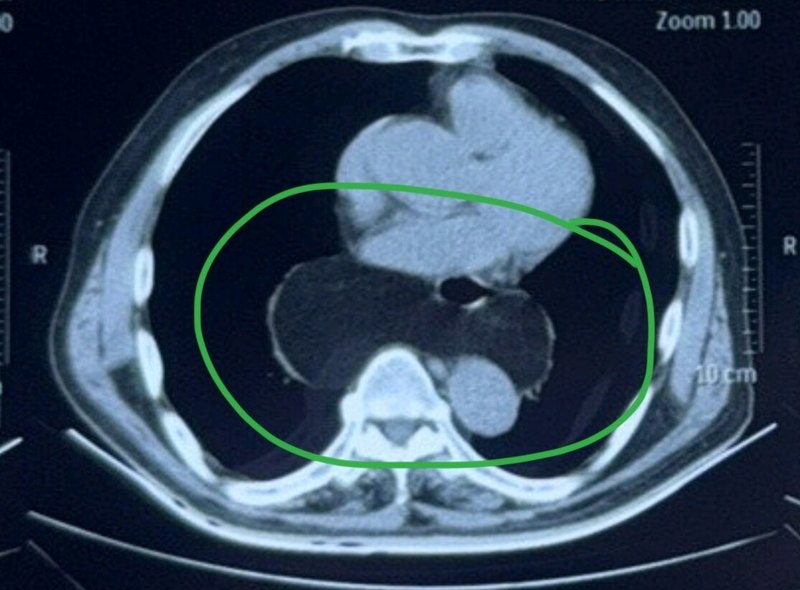

一位家住東北的老先生在女兒的陪伴下來(lái)天津看病,老先生最近感覺(jué)下胸部有些疼痛,雖然不是很?chē)?yán)重,但這種感覺(jué)讓他有些擔(dān)心。他在當(dāng)?shù)蒯t(yī)院拍了CT,發(fā)現(xiàn)了肺里有結(jié)節(jié),他特地來(lái)天津,看看自己的胸疼是不是肺結(jié)節(jié)引起的,需不需要手術(shù)切除?我仔細(xì)閱讀他的胸部CT,他的肺結(jié)節(jié)已經(jīng)五毫米,邊緣很光滑,看起來(lái)考慮惡性的,胸疼和肺結(jié)節(jié)關(guān)系不大。我注意到他的主動(dòng)脈裂孔疝比較嚴(yán)重,胸疼可能與此有關(guān)。主動(dòng)脈裂孔疝,指部分胃或其他腹腔臟器通過(guò)膈肌裂孔進(jìn)入胸腔縱隔內(nèi)。當(dāng)膈肌的裂孔周?chē)M織變薄弱或松弛,同時(shí)腹腔內(nèi)壓力升高時(shí),就可能引發(fā)該病。這個(gè)病是有可能引起胸痛的。一方面,部分胃組織疝入胸腔,可能會(huì)對(duì)周?chē)M織造成壓迫;另一方面,可能引發(fā)反流性食管炎,反流物刺激食管黏膜,也會(huì)導(dǎo)致疼痛。疼痛性質(zhì)多樣,如隱痛、脹痛、燒灼感疼痛等,部位也不固定,可在胸部正中、偏左或偏右等位置。